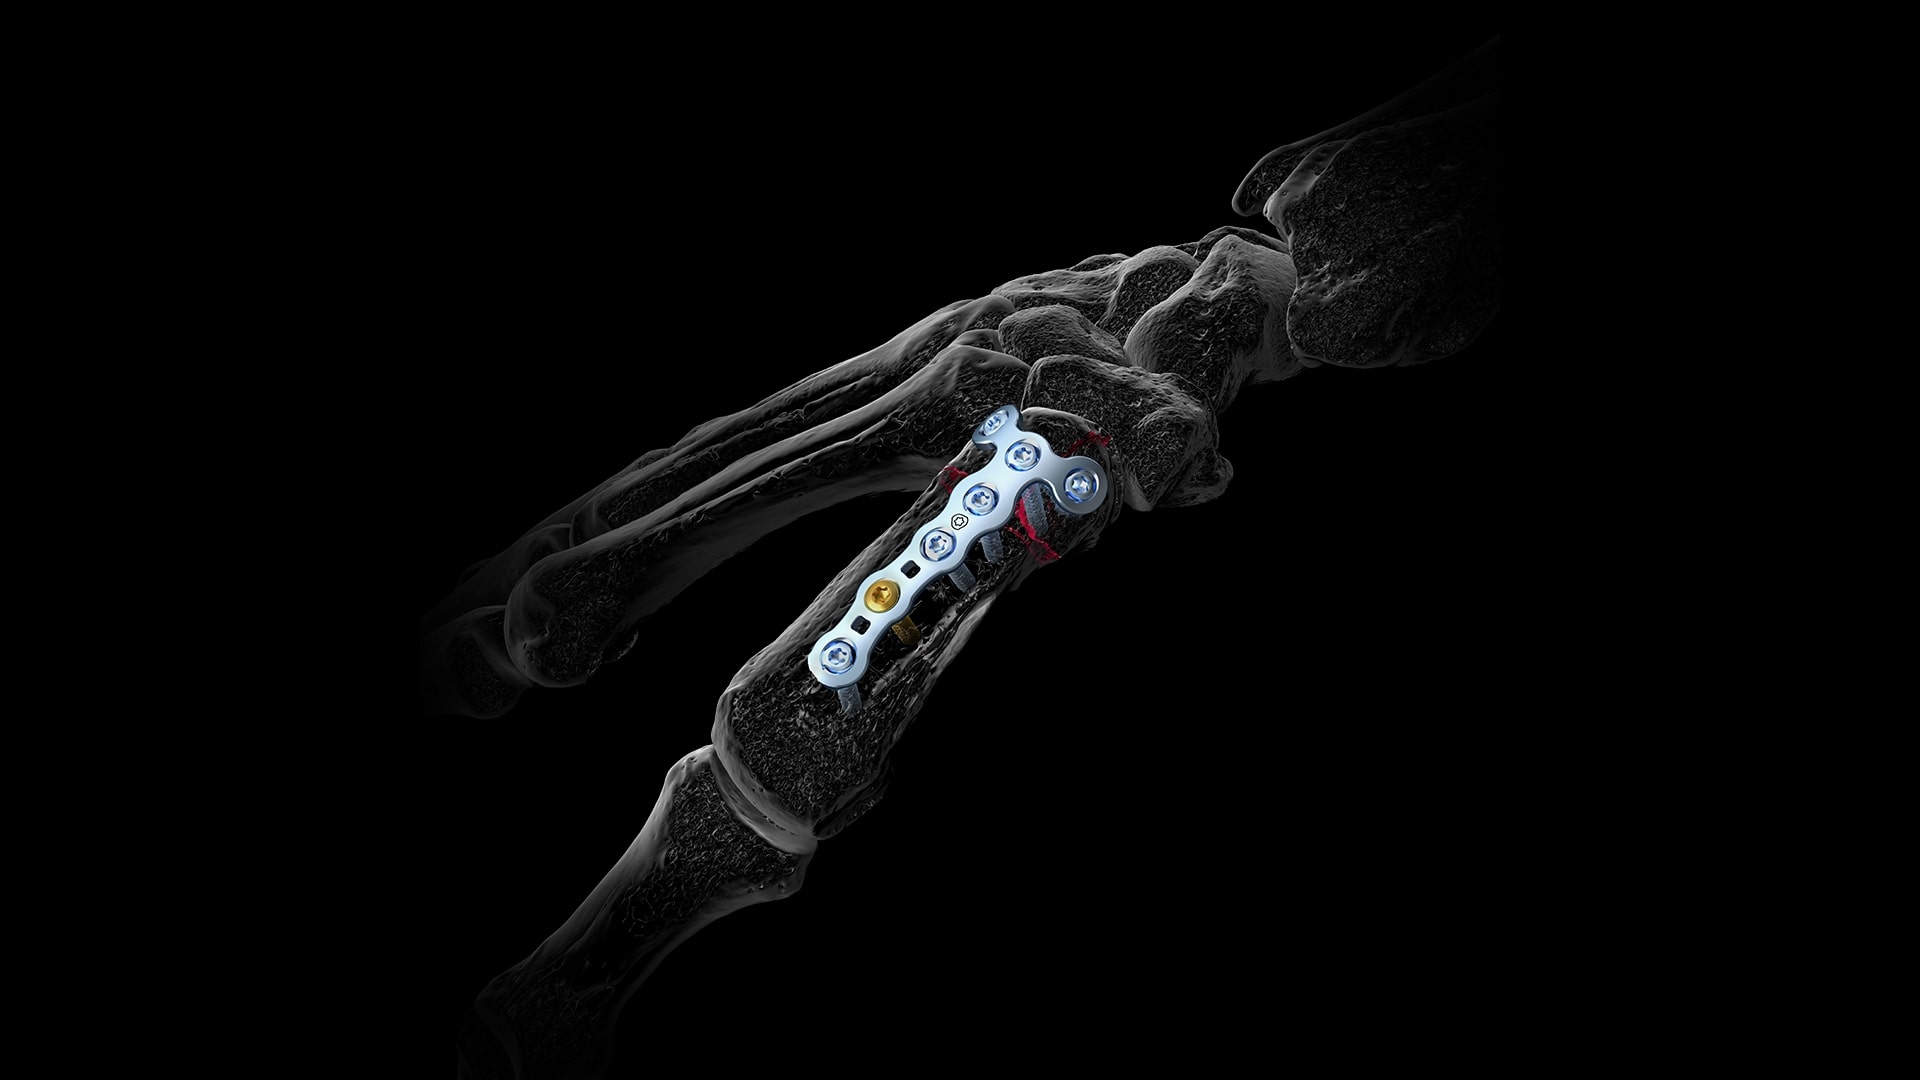

Eine konservative Therapie kann bei undislozierten Frakturen ohne Abkippungstendenz (stabile Frakturen) durchgefürt werden. Die Gipstragedauer ist auf 4 Wochen befristet. Eine opertive Therapie muss bei instabilen, mehrfragmentären Frakturformen durchgeführt werden. Auch Fehlstellungen wie Rotationsfehlstellungen stellen eine OP Indikation dar.

Als konservative Maßnahme kann eine Ruhigstellung sowie Schmerzmitteleinnahme erfolgen. Bei Ausbleiben einer Knochenheilung kann eine Operation durchgeführt werden. Ausgewählte Operationsbeispiele sind die Mittelhandknochenverplattung.

Was geschieht bei diesem Eingriff genau?

Aufgrund der Vielzahl an unterschiedlichen Operationsmöglichkeiten, besprechen wir gemeinsam das weitere Vorgehen und welche Operationsmethode in Ihrem Fall die Richtige ist. Sollte es notwendig sein intraoperativ die geplante Methode zu ändern wird Ihnen das im Vorfeld exakt erklärt bzw. wenn der Eingriff in Lokalanästhesie durchgeführt wird, direkt mit Ihnen geklärt.